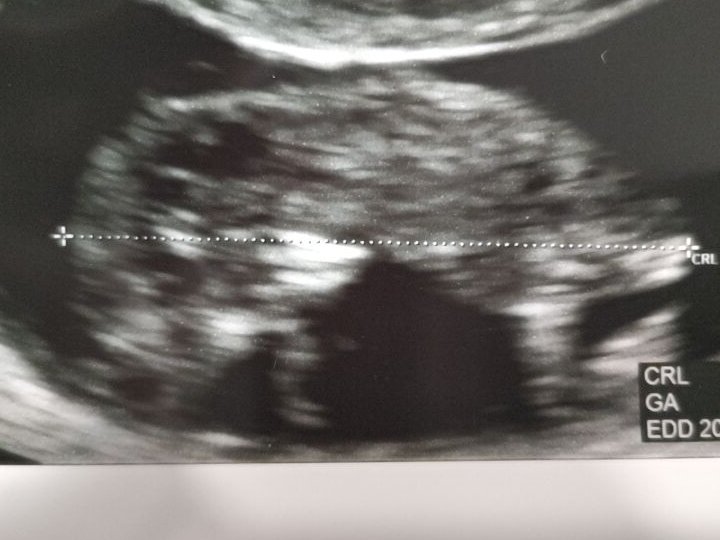

約11週になりました😊

身長約6cm👶

だいたい一般的な名刺のサイズくらいの大きさですかね